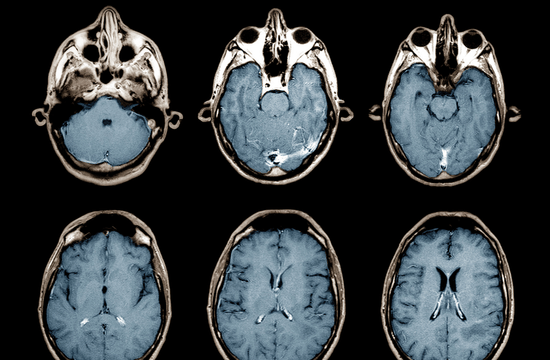

MRI מוח/ ראש

CT ראש + מוח